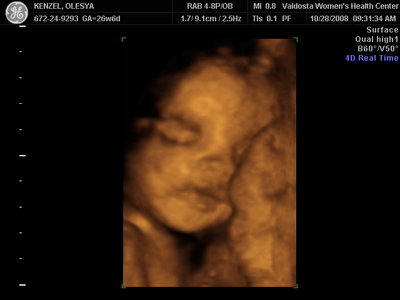

Ксюнь, а мы вообще не поняли. Она на всех фотках разная, да еще размытость такая. Пуповина то на носу болталась, то руками-ногами закрывалась. Главное что четкости нет совсем. Лоб у мужа тоже большой, а носы и губы зачастую на 3Д-4Д выходят разамазанно-пухло-приплюснутыми Поставлю для наглядности фотку моей средней-Джианки с 3Д УЗИ, там видно черты намного лучше и она на себя ту похожа сейчас, хотя родилась мне совсем на фото УЗИ не казалась похожей.

| Вложения: |

KENZEL,OLESYA_3.JPG [ 56.84 КБ | Просмотров: 1410 ]

Еще одна Джианнка:

KENZEL,OLESYA_5.JPG [ 60.02 КБ | Просмотров: 1495 ]